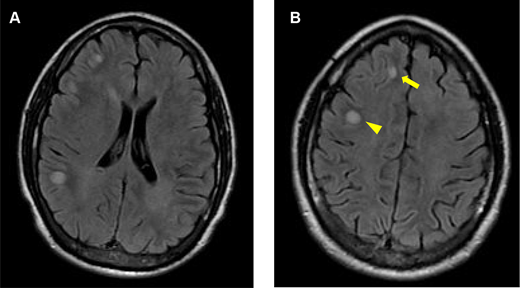

The patient’s magnetic resonance imaging (MRI) of the brain at 5 months after the seizure onset. He had no symptoms. Axial fluid-attenuated inversion recovery (FLAIR) imaging of the brain shows new poorly demarcated hyperintense lesions in the left frontoparietal white matter (arrows).